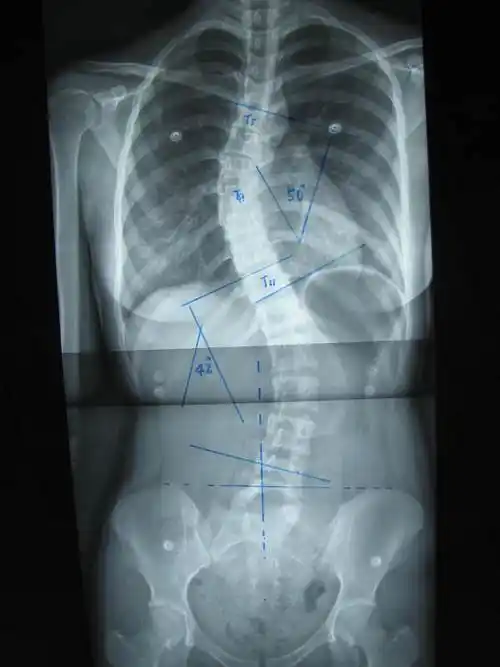

河南省人民医院的骨科专区 范护师 人体脊柱构造 c颈7 t胸12 l腰5 s

后路手术矫形治疗青少年特发性脊柱侧凸畸形附图片资料